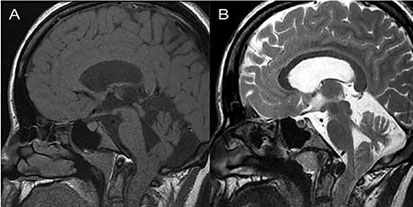

Se realizó resonancia magnética (RM) de la columna craneocervical, que demostró ptosis de las amígdalas cerebelosas sin siringe cervical (figura 1). La corrección quirúrgica fue planeada, y consistió en una laminectomía cervical C1, y craniectomía suboccipital con duroplastia. La paciente toleró bien el procedimiento, en el posoperatorio la paciente presentó una evolución satisfactoria, y fue dada de alta en el 7º día. En el seguimiento a los 3 años, la paciente era discretamente asintomática y no tenía hallazgos neurológicos anormales.